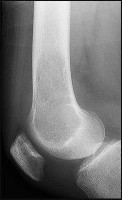

Figures 5a and 5b are the radiographs of a 74-year-old man with poorly differentiated squamous cell carcinoma of the lung. He has had an uneventful recovery after undergoing a wedge resection of his left upper lobe 6 months ago. He is experiencing left lateral knee pain, and a whole-body positron emission tomography/CT scan shows no avid area other than the lateral left distal femur. This patient has needed to use a wheelchair for 3 weeks because of his pain. You discuss these treatment options: aggressive curettage, local adjuvant treatment, cementation, and prophylactic fixation vs distal femoral resection and megaprosthesis total knee arthroplasty reconstruction. You should tell him that

Distal femoral megaprosthetic reconstruction after tumor resection is a reliable oncologic procedure, but 5-year implant survival is as low as 74% with an approximate 8% deep infection rate. The amputation rate is as high as 8% because of infection or recurrence, and there is an overall 18% revision rate. More than 10% of distal femoral megaprosthetic reconstructions are performed to address metastatic disease.

Fixation failure and infection may occur with either procedure. Radiation may not be recommended after a megaprosthesis reconstruction unless margins are not free of tumor. Either operation may be equally successful in returning patients to functional activities. Overall disease-free survival is related to the aggressiveness of the tumor and not the type of reconstruction performed.